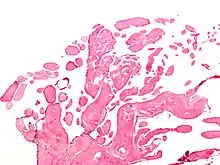

| Low magnification micrograph of an excised aortic valve papillary fibroelastoma showing the characteristic avascular branching papillae, H&E stain | |

Papillary fibroelastoma are typically found and accurately diagnosed by imaging. The diagnosis is confirmed by pathology. Histologically, papillary fibroelastomas have branching avascular papillae, composed of collagen, that are covered by endothelium.